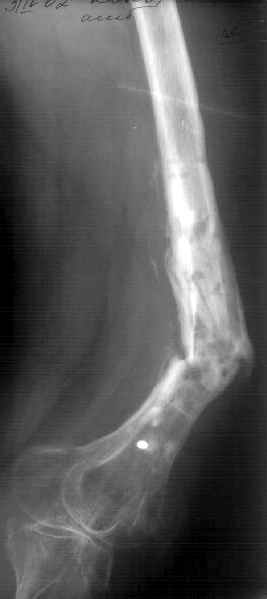

К нам поступила худощавая женщина 48 лет, которой года 2,5 назад был выполнен остеосинтез бедра пластинкой в одной из горбольниц. В сентябре 2001 г. пластинку убрали. Начала разрабатывать движения, ходила с тростью. С января этого года

отмечает усугубление деформации бедра и улучшение движений "в коленном суставе". При осмотре имеетсяподвижность на месте перелома (псевдартроза), больше в сагиттальной плоскости. Рентгенограммы в приложении(фас; профиль). Полностью угол, открытый кзади, под нагрузкой не устраняется. "Сгибается" еще градусов на 30. Ходит с тростью. Надколенник неподвижен, в суставе, видимо, движений нет совсем. В любом случае надо, видимо, начинать с восстановления оси и стабилизации бедра. Как окончательный фиксатор хотелось бы использовать интрамедуллярный стержень. Можно ли в данном случае устранить угол одномоментно? Или лучше дозированно? Нужна ли костная пластика местно? Не стоит ли пойти на мобилизующую операцию в один этап? Если да, то какую?Может быть, есть еще какие-то моменты, которые следует учесть?Спасибо заранее.-- Best regards, Alexander N. Chelnokov

The pt has 20 degree of varus and 30-40 degree of procurvatum Acute correction may compromise the nurovascualr structures. Moreover xray shows evidence of infection and she has almost knee range of motion.

Не сформировалось у нас убежденности в целесообразности мобилизующей операции в один этап с остеосинтезом. Решили пойти по максимально щадящему пути. Первым этапом наложили аппарат. Снимок (см. приложение) сделан в положении максимально возможной коррекции оси, достигаемой одномоментно исправлением "об коленку" с ручным растягиванием колец сзади. Варус удалось убрать, а вот антекурвацию, от греха, лучше устраним дозированно, дней за 7-10. Потом планируем антеградный закрытый интрамедуллярный остесинтез. Буду признателен за отклик.